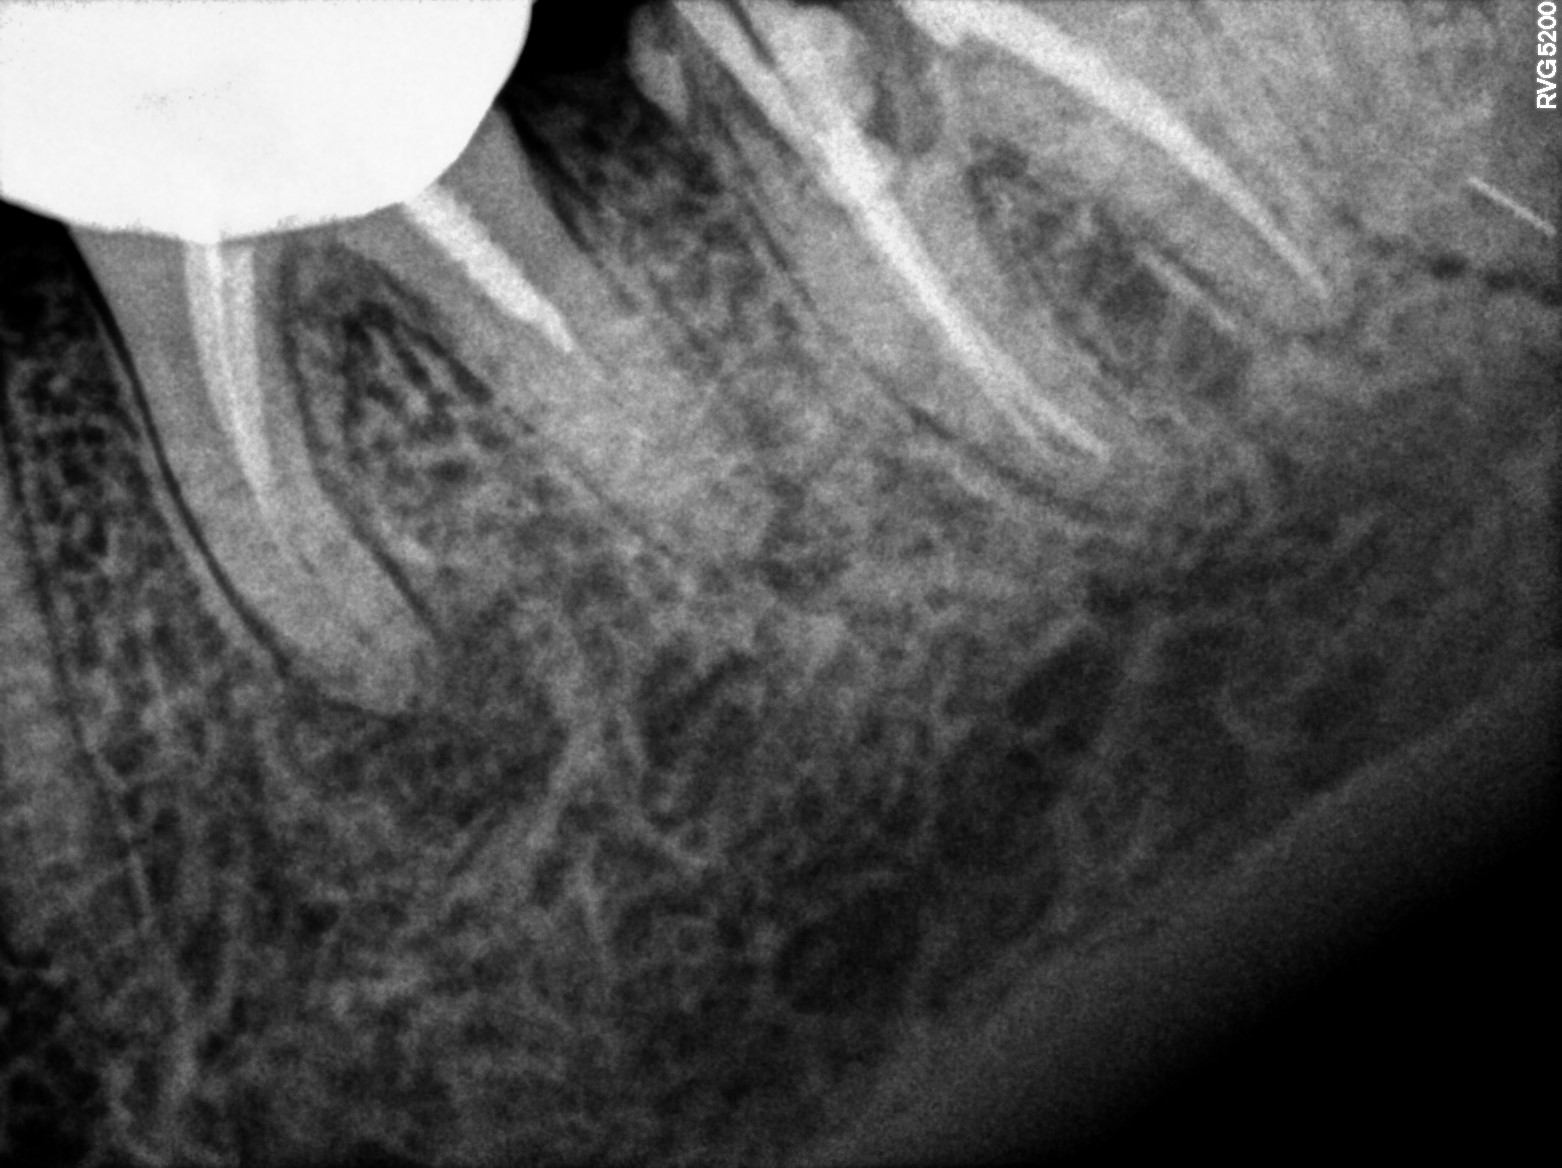

Dental Radiographs FHIR: DocumentReference · LOINC 24641-7

R56 (2).jpg

24641-7